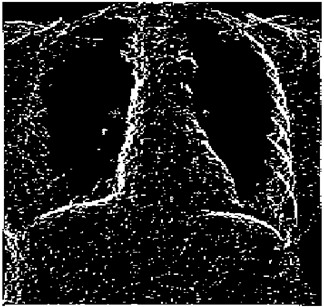

Table 10. Edge-detected image of “X-ray 1” after binarization for different noises.

NoiseCannyStandardSmooth

No noise Mathematics 10 02421 i072 Mathematics 10 02421 i073 Mathematics 10 02421 i074

G(0.001) Mathematics 10 02421 i075 Mathematics 10 02421 i076 Mathematics 10 02421 i077

G(0.002) Mathematics 10 02421 i078 Mathematics 10 02421 i079 Mathematics 10 02421 i080

G(0.003) Mathematics 10 02421 i081 Mathematics 10 02421 i082 Mathematics 10 02421 i083

I(0.25%) Mathematics 10 02421 i084 Mathematics 10 02421 i085 Mathematics 10 02421 i086

I(0.5%) Mathematics 10 02421 i087 Mathematics 10 02421 i088 Mathematics 10 02421 i089

I(1%) Mathematics 10 02421 i090 Mathematics 10 02421 i091 Mathematics 10 02421 i092

Table 10 shows the following:

• In all cases, the Canny edge detector detects more edge pixels than both fuzzy compositions.

• As the level of noise increases, Canny and standard composition become adversely affected by the noise, and still more edges are detected by Canny; however, most of the detected edges by Canny are misdetections due to the impact of noise. As is obvious from this table, the smooth composition provides a better image with reduced noise density.

• In all cases, the PFOM value for the smooth composition is always greater than the PFOM value for the standard composition, according to Table 6.